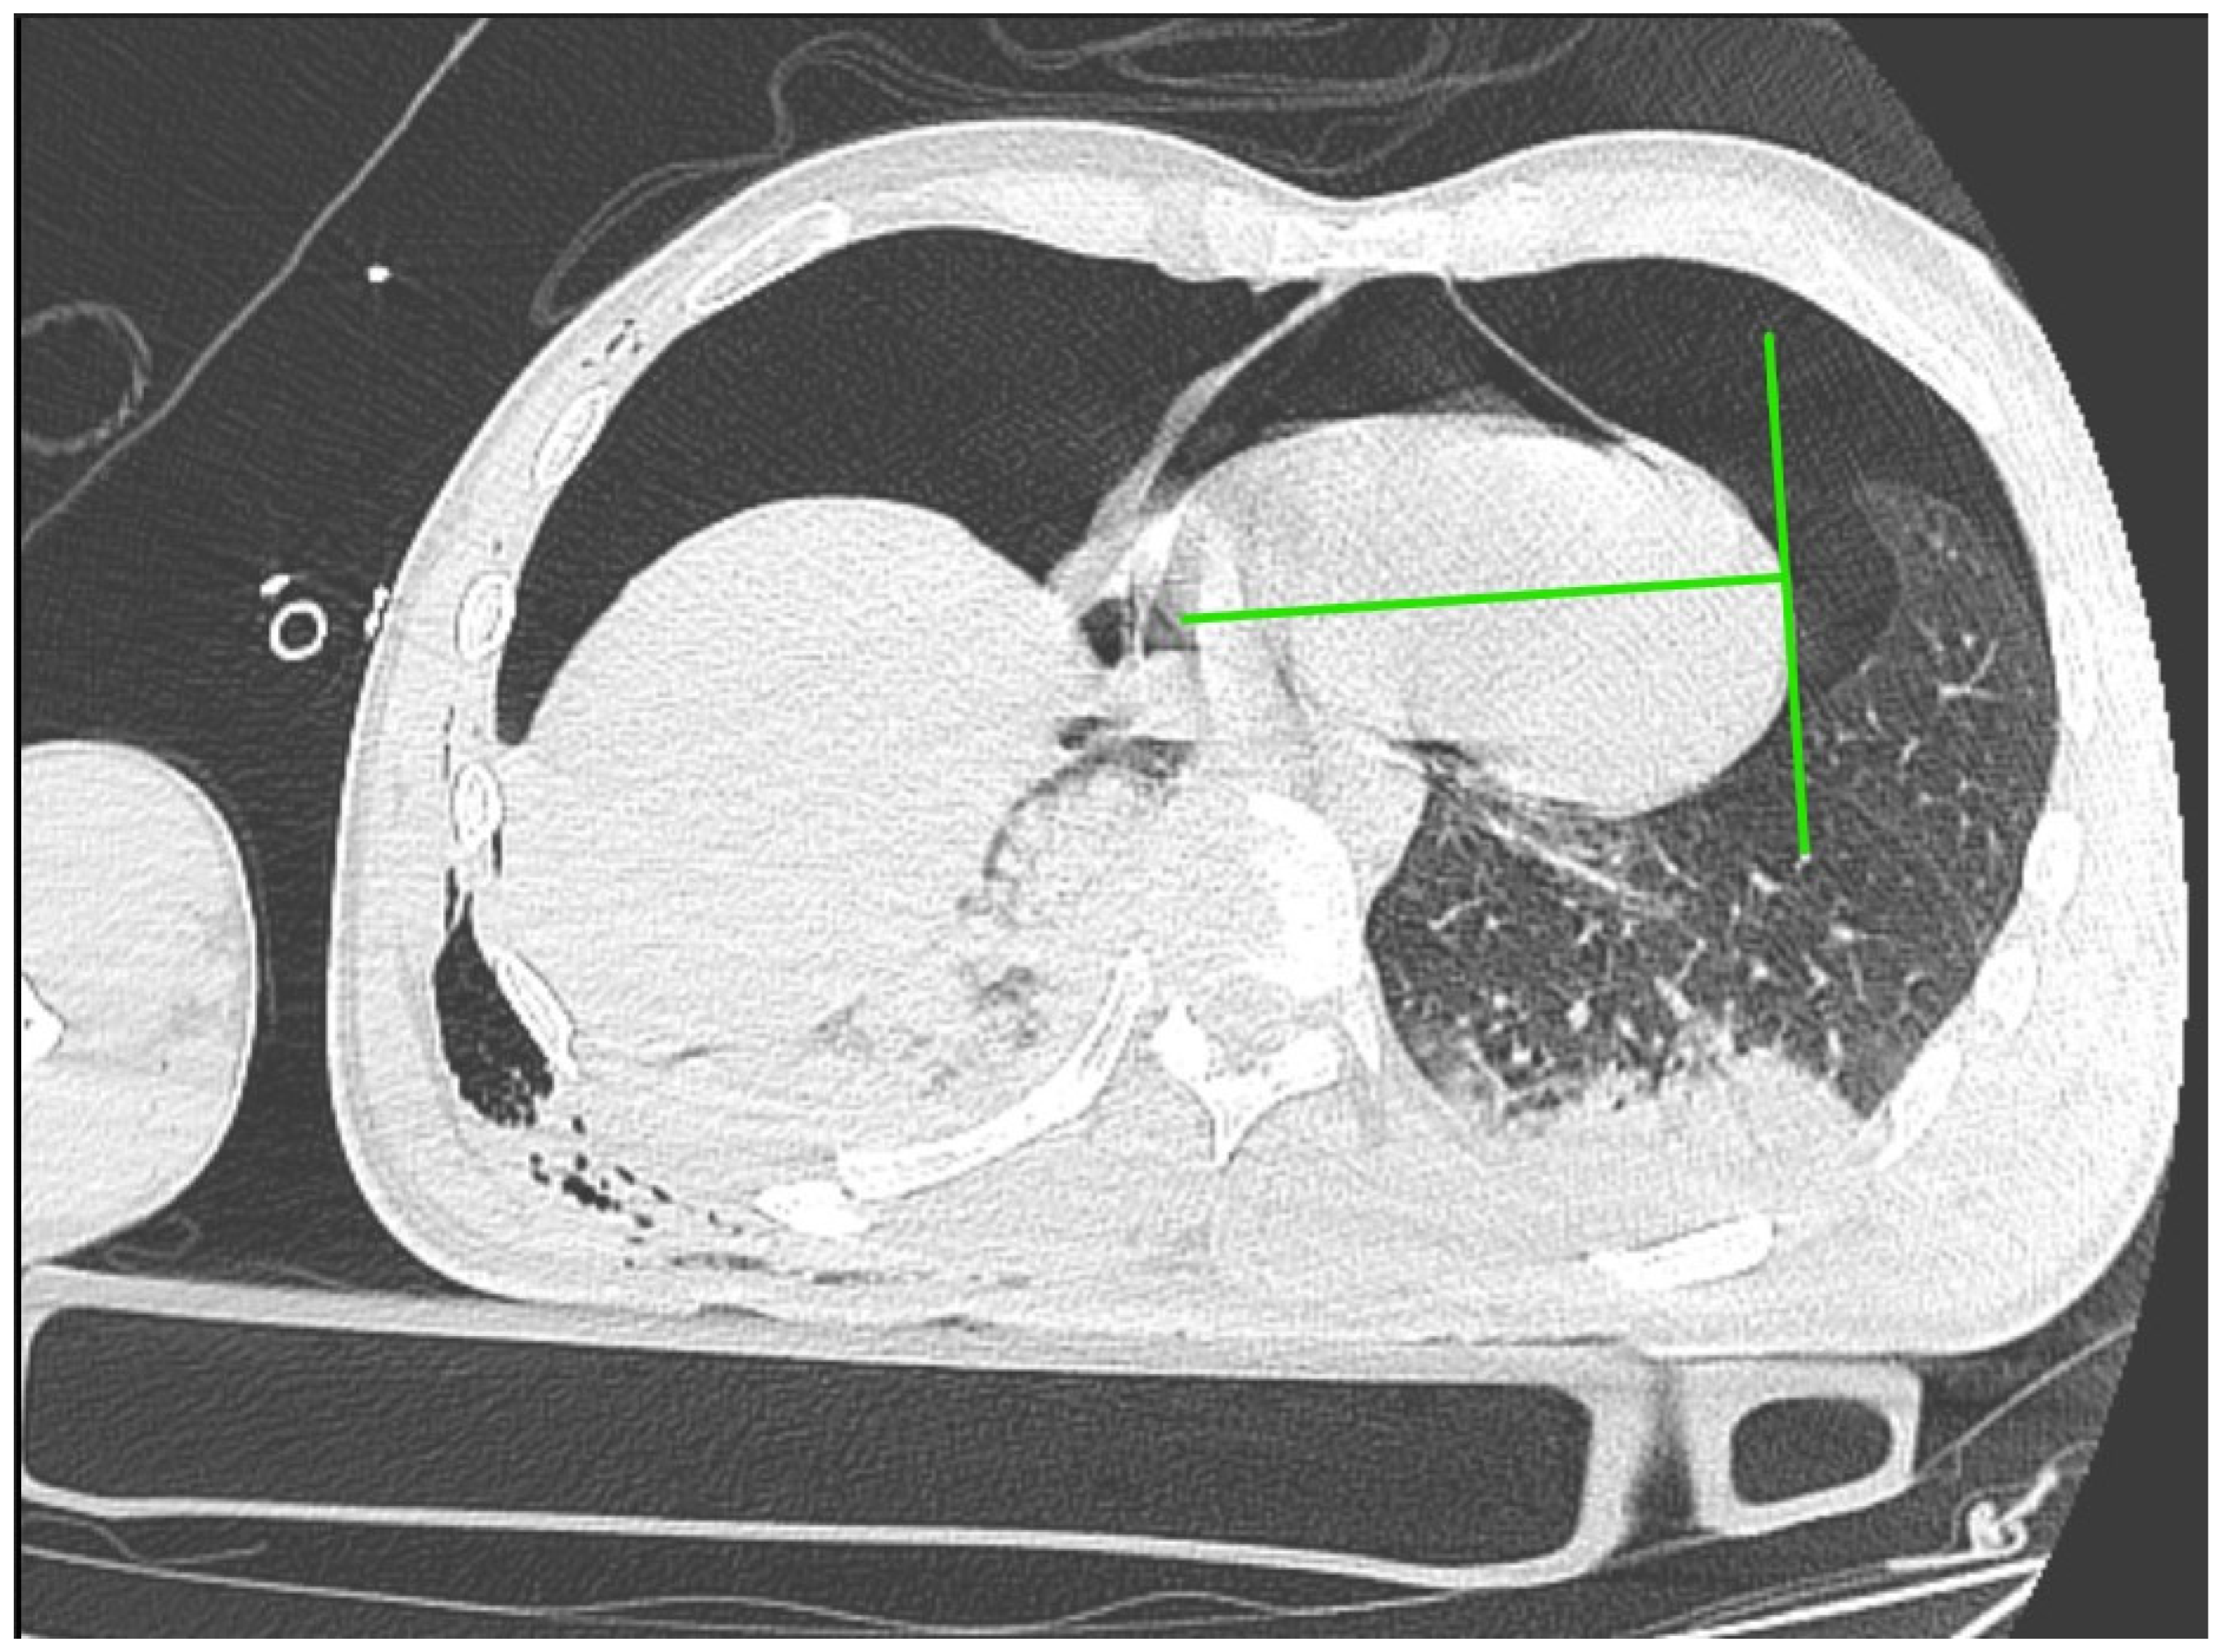

Immediately after decompression, the blood pressure was 134/85 mmHg, the heart rate was 105 bpm, and the saturation was 92%. The critical parameters from the blood gas analyzer just after the decompression of pneumothorax are as follows (11:15 p.m.): pH 7.016, pCO2 45.2 mmHg, pO2 107 mmHg, HCO3 11.6 mmol/L, BE −19.4, anion gap 19.4 mmol/L, and hemoglobin 15.0 g/dL (after transfusion of three units of red blood cells). Laboratory blood tests showed a level of troponin 15,158.657 pg/mL. In the next 30 min, the blood pressure was 85/50 mmHg. Catecholamine infusion was initiated, fluid therapy was continued, and point-of-care ultrasound diagnostics were repeated, Still, we could not obtain the heart from any ultrasound window. A new CT scan was performed with no contrast, and there was bilateral pneumothorax small pneumopericardium in the pericardial cavity (Figure 2 and Figure 3). Drainage of the left pleural cavity was performed. The right drain was oscillating, but it was no longer functional and was trapped in the lung fissure between the expanding lobes of the right lung, which was seen on CT scans. The right pleural drain was replaced, which resulted in an improvement in the patient’s condition. However, he still required the use of catecholamine.

Approximately 50 mL of air was obtained, which resulted in a significant reduction in symptoms despite the persistence of pneumopericardium in the CT scan but without the signs of elevated pressure in the pericardial sac (Figure 6).

Figure 2. CT scan of pneumothorax and pneumocardium after a pneumopericardial decompression—scan at the level of the diaphragm.